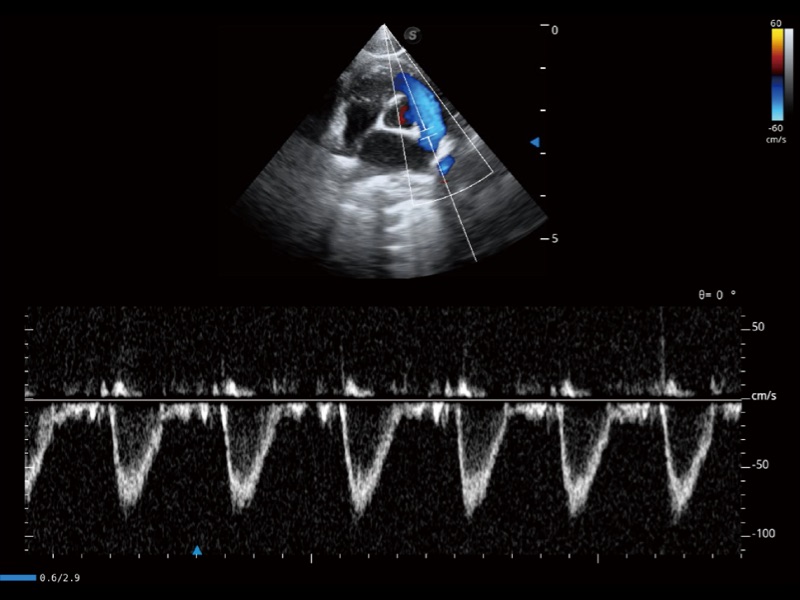

(猫)肺动脉血流频谱

(犬)左室长轴血流

• AMM 解剖M型

通过360度任意调节3条M型取样线,在同一心动周期上观察心脏不同位置的运动曲线,得到准确的心功能测量数据,有效评估心肌运动及左心室功能。

• TDI 组织多普勒成像

实时用颜色表示心肌组织运动,观察和定量组织的运动情况,对快速检测与评估心肌的灌注和活性、电传导及心肌收缩和舒张功能等均能提供重要的诊断信息。